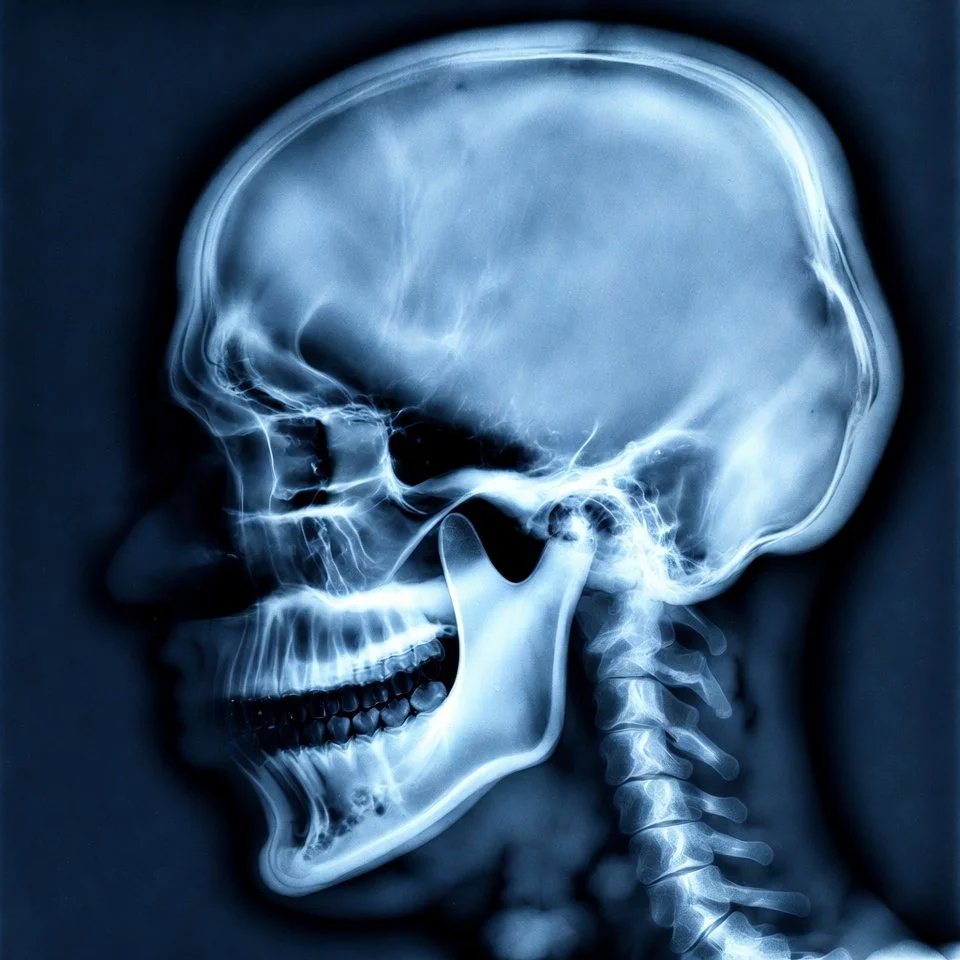

Con nuestros equipos podemos obtener imágenes panorámicas, de perfil y en 3 dimensiones con gran nitidez, gracias a su sistema innovador que sigue perfectamente la curva natural de tus dientes, consiguiendo ver toda tu boca de la forma más clara posible, enfocándonos solo en lo que realmente importa: diagnósticos mucho más precisos con la menor radiación necesaria.